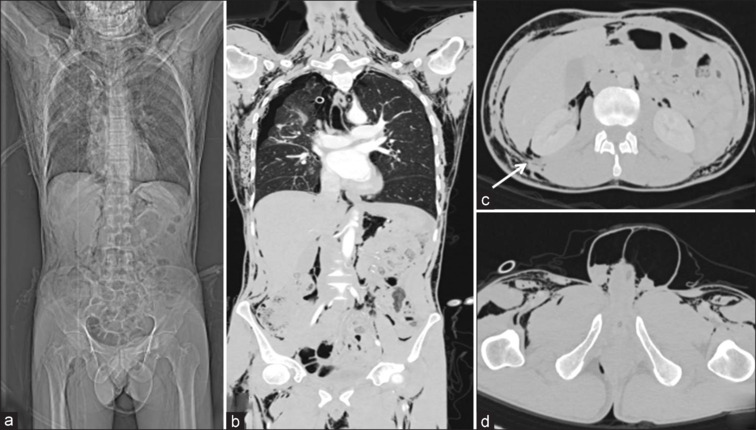

Air Everywhere without Bowel Injury.

空气无处不在,却不会伤及肠道。